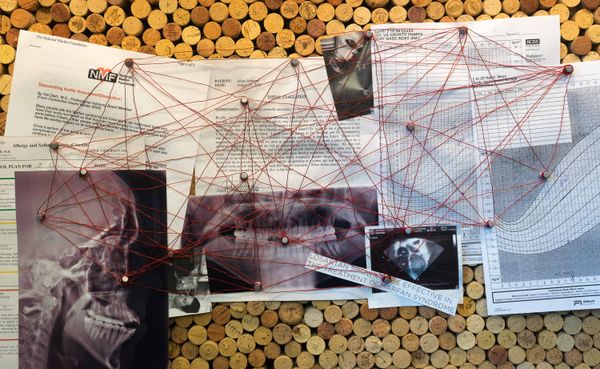

I remember reading about Marfan Syndrome in my high school biology class, the textbook featuring a picture of a skinny boy looking like a deer caught in the headlights. Since getting diagnosed at age five, I’ve been dissatisfied with the cold, clinical imagery surrounding the connective tissue disorder. Even You, Metal Back is an exploration of the intersection of physical pain, mental health, religion, and healing. A self-portrait, if you will, unearthing anxieties around corporality while living with this chronic condition.